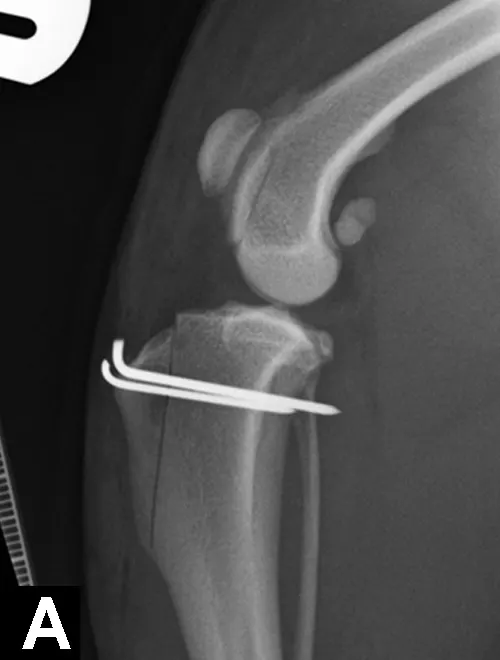

The response to surgical treatment can vary, and development of OA continues in the joint despite treatment. Other surgical options include subtotal coronoid ostectomy (SCO), sliding humeral osteotomy (SHO), proximal abducting ulnar osteotomy (PAUL), or biceps ulnar release procedure (BURP).

Management of joints with significant OA can also be nonsurgical (eg, weight loss, analgesics, joint supplements, exercise modification, physiotherapy) or surgical (eg, canine unicompartmental elbow [CUE] replacement, total elbow replacement). Removal of the cartilage flap with debridement of the subchondral bone arthroscopically is also recommended for OCD lesions. The UAP can be reattached and compressed to the proximal ulna via a lag screw if degeneration of the fragment is not advanced. If fragment degeneration is advanced, however, removal by arthrotomy is recommended. If joint incongruency is evident, proximal ulnar osteotomy/ostectomy may be performed to improve congruency.